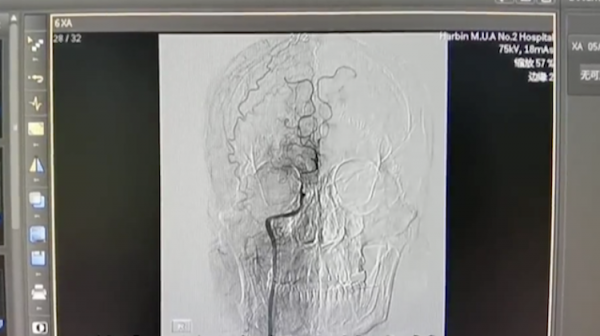

哈醫大二院神經外科三病房主任醫師王洪軍介紹:“患者特別年輕,我們就想梗塞的原因到底是什麼,所以進行了腦血管造影的檢查。看到有動脈閉塞,滋生了很多細小的血管,我們確診就是煙霧病。”

煙霧病是顱內血管一種畸形狀態,因為患者的血管太細了,在造影檢查下甚至都分不出來支數,好像一團煙霧,因此得名。煙霧病的病因尚不明確,很多患者都是腦梗或腦出血發作才檢查出來。